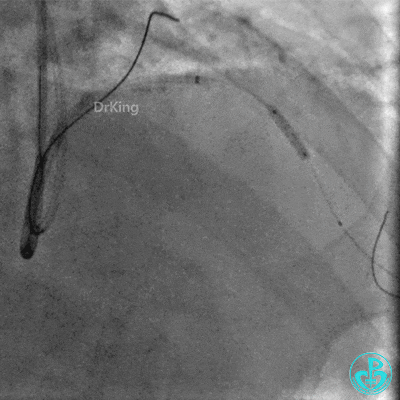

撤回逆向导丝及微导管造影,钝缘支远端侧支造影剂渗漏,局部造影剂滞留范围不断扩大。

明胶在血管怎么降解并发症丨前降支CTO同侧逆向开通时侧支血管破裂,弹簧圈联合明胶海绵封堵_https://www.jmylbn.com_新闻资讯_第31张

前降支末梢经微导管释放3.0×2.5mm弹簧圈封堵破口。

钝缘支经微导管释放5.0×5.5mm弹簧圈封堵破口。